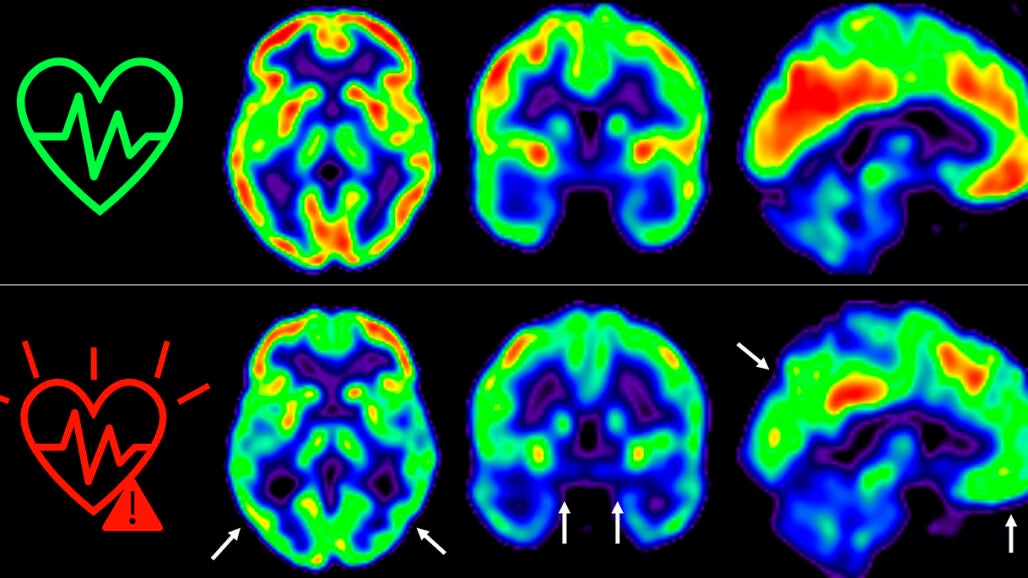

El equipo de Fuster, liderado por Marta Cortés Canteli y Juan Domingo Gispert, han seguido a estos individuos a lo largo de 5 años y han encontrado que aquellos que mantienen un riesgo cardiovascular elevado durante todo este tiempo sufren una disminución aún mayor del metabolismo cerebral medido a través de técnicas de imagen como tomografía por emisión de positrones (PET).

"Hemos detectado un declive metabólico cerebral tres veces mayor que el de personas que se mantienen en bajo riesgo cardiovascular", señala Catarina Tristão-Pereira, primera firmante del nuevo artículo y becaria INPhINIT de la Fundación "la Caixa".

Además, el equipo del CNIC descubrió que la progresión de la aterosclerosis subclínica en las carótidas durante estos 5 años se relacionaba con una disminución del metabolismo en regiones cerebrales vulnerables a la enfermedad de Alzheimer, de manera aditiva al efecto de los propios factores de riesgo cardiovascular.